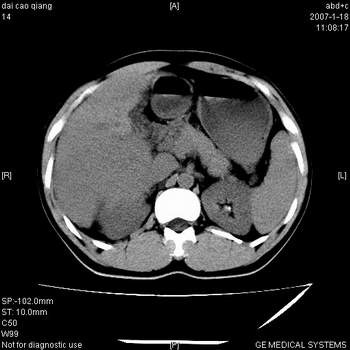

符合巨块型肝癌表现:

1、平扫低密度,增强后表现为快进快出。

2、动脉期可见迂曲的动脉供血血管

3、并可见门静脉右支癌栓形成

4、可见假包膜

5、腹主动脉旁结节影,考虑肿大淋巴结。

典型的肝右叶巨块型肝癌破裂、门脉瘤栓形成。

肝右叶巨大不均匀低密度肿块,前缘有假包膜,增强明显的呈快进快出表现,门脉右支有癌栓,病人虽然年轻但还是首先考虑肝右叶巨块形肝癌,病人血象高只能说有合并感染。不支持肝脓肿。